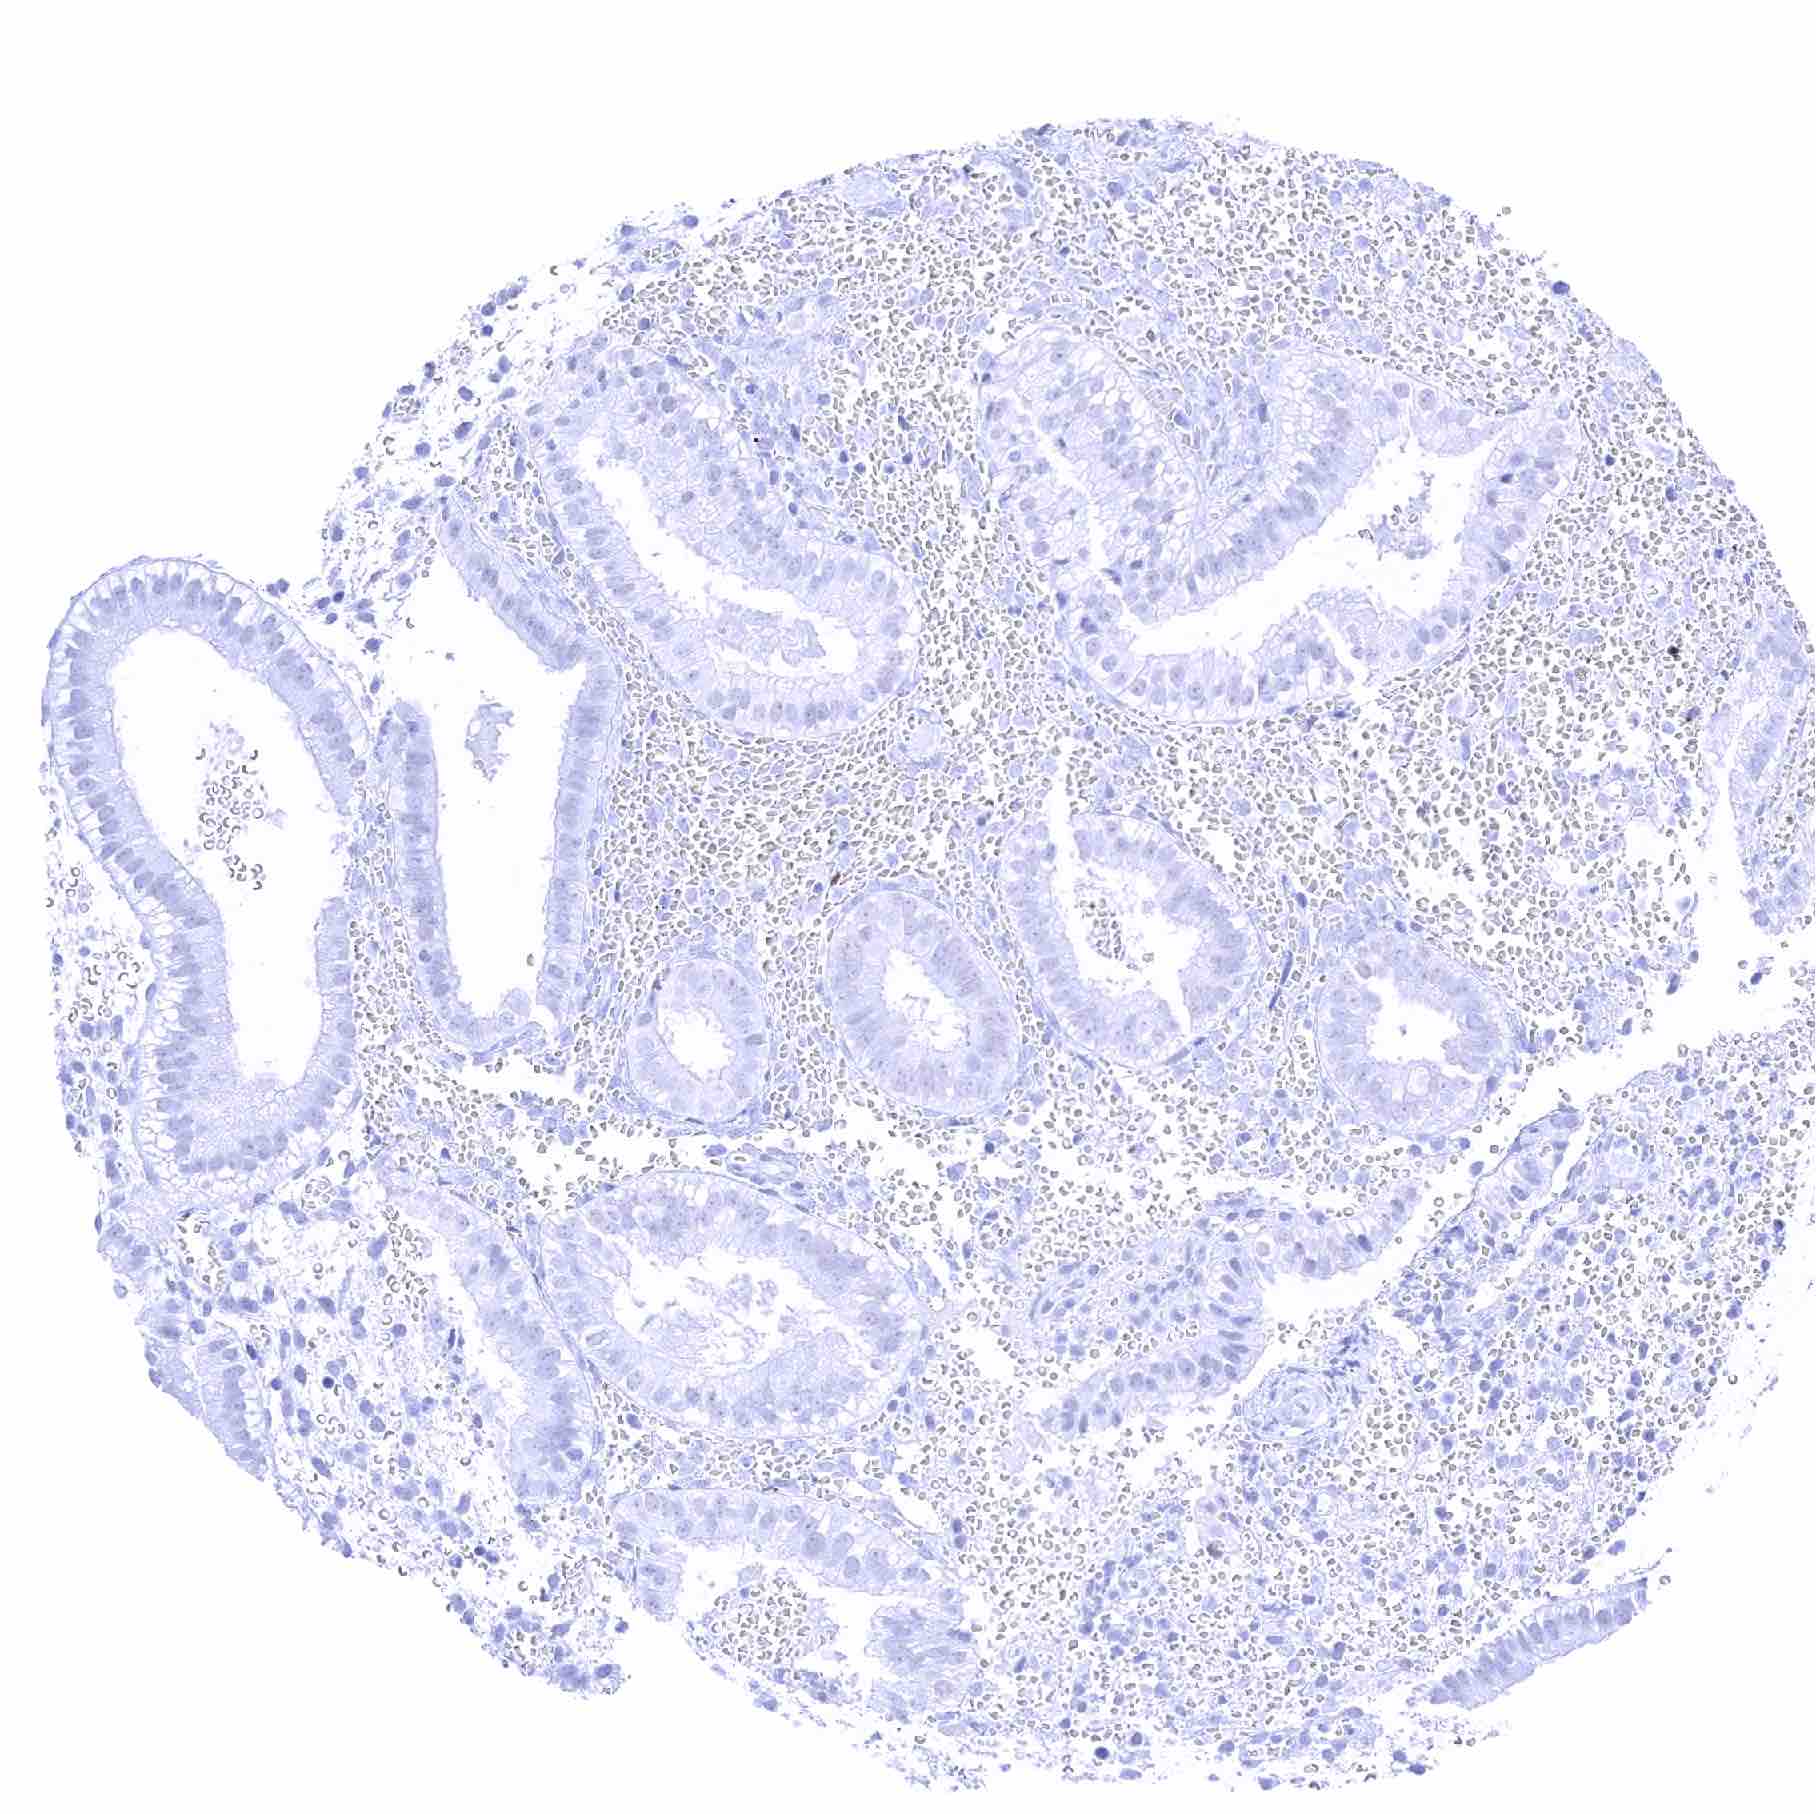

Stomach, antrum – Significant SOX2 staining of a fraction of glandular cells

Stomach, antrum